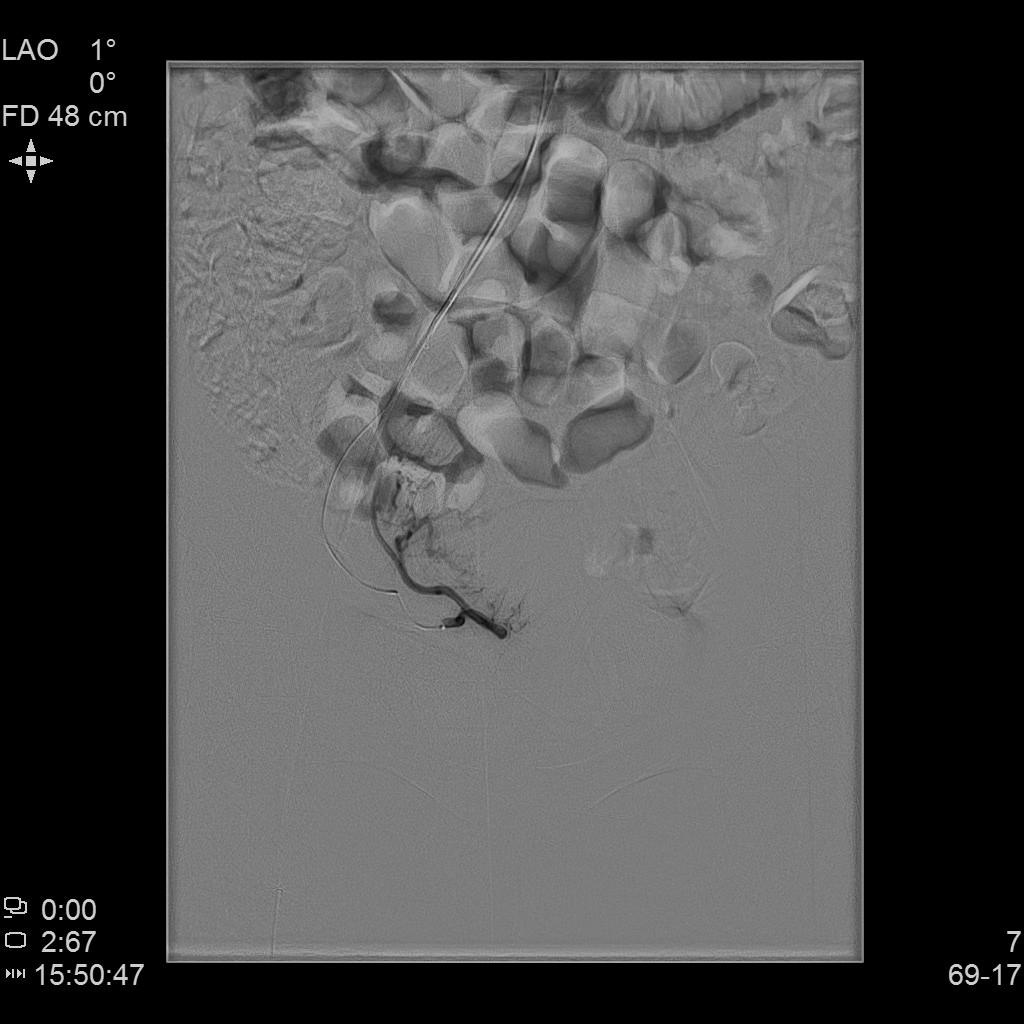

- 插管至左侧子宫动脉,显示子宫左侧病灶情况

左侧子宫动脉造影